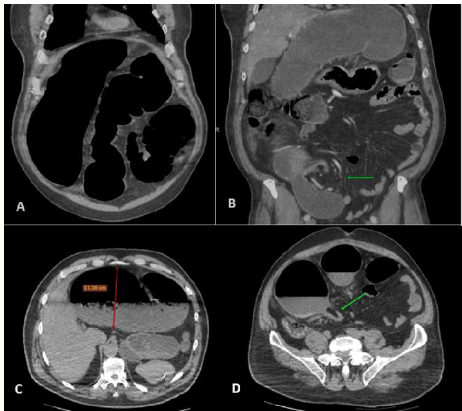

Beak and Whirl Sign: A Hallmark of Sigmoid Volvulus

Hajar Zebbakh, Zakaria Toufga, Abir Lemrabet, Aziz Hommadi and Jamal El Fenni. 7(4): 15-18.